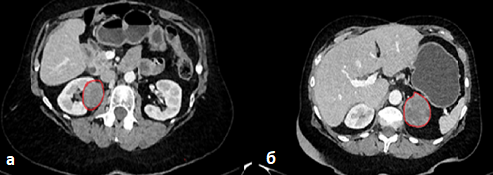

Пациентка обследована, и при выполнении комбинированной позитронно-эмиссионной и рентгеновской компьютерной томографии (ПЭТ-КТ) с 18-фтордезоксиглюкозой выявлены массивное образование правого надпочечника 112×88 мм, сдавливающее окружающие органы, а также наличие опухолевого тромба, обтурирующего просвет нижней полой вены и распространяющегося вплоть до правого предсердия (рис. 1).

Рис. 1. ПЭТ-КТ от 07.2020: a–c – образование правого надпочечника 112×88 мм, сдавливающее окружающие органы; d – опухолевый тромб, заполняющий просвет нижней полой вены.

Fig. 1. PET-CT dated July 2020: a–c – right adrenal gland mass of 112×88 mm, compressing the surrounding organs; d – tumor thrombus filling the lumen of the inferior vena cava.